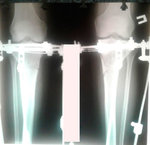

на фиксации